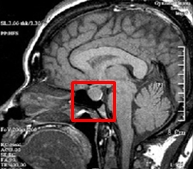

사람의 내분비선에는

뇌하수체, 갑상선, 부갑상선, 부신, 췌장, 정소와 난소가 있는데

그 중 가장 중요한 역할을 하는 곳은

뇌 속에 있는 작은 기관인 ‘뇌하수체’ 입니다.

이 뇌하수체는 시상하부에 의해 조절되는데

내 몸의 상태와 환경에 대한 정보를 받아들여

표적 기관인 갑상선, 부신, 성선 등에 신호를 보내

각각의 기관에서 분비하는 호르몬을 분비하게 됩니다.